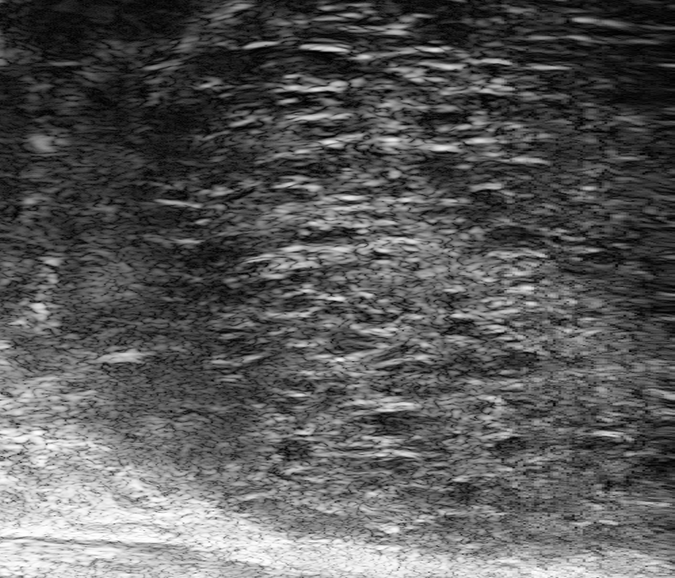

PRI-MUS 2

Hyperechoic with/without ductal patches.